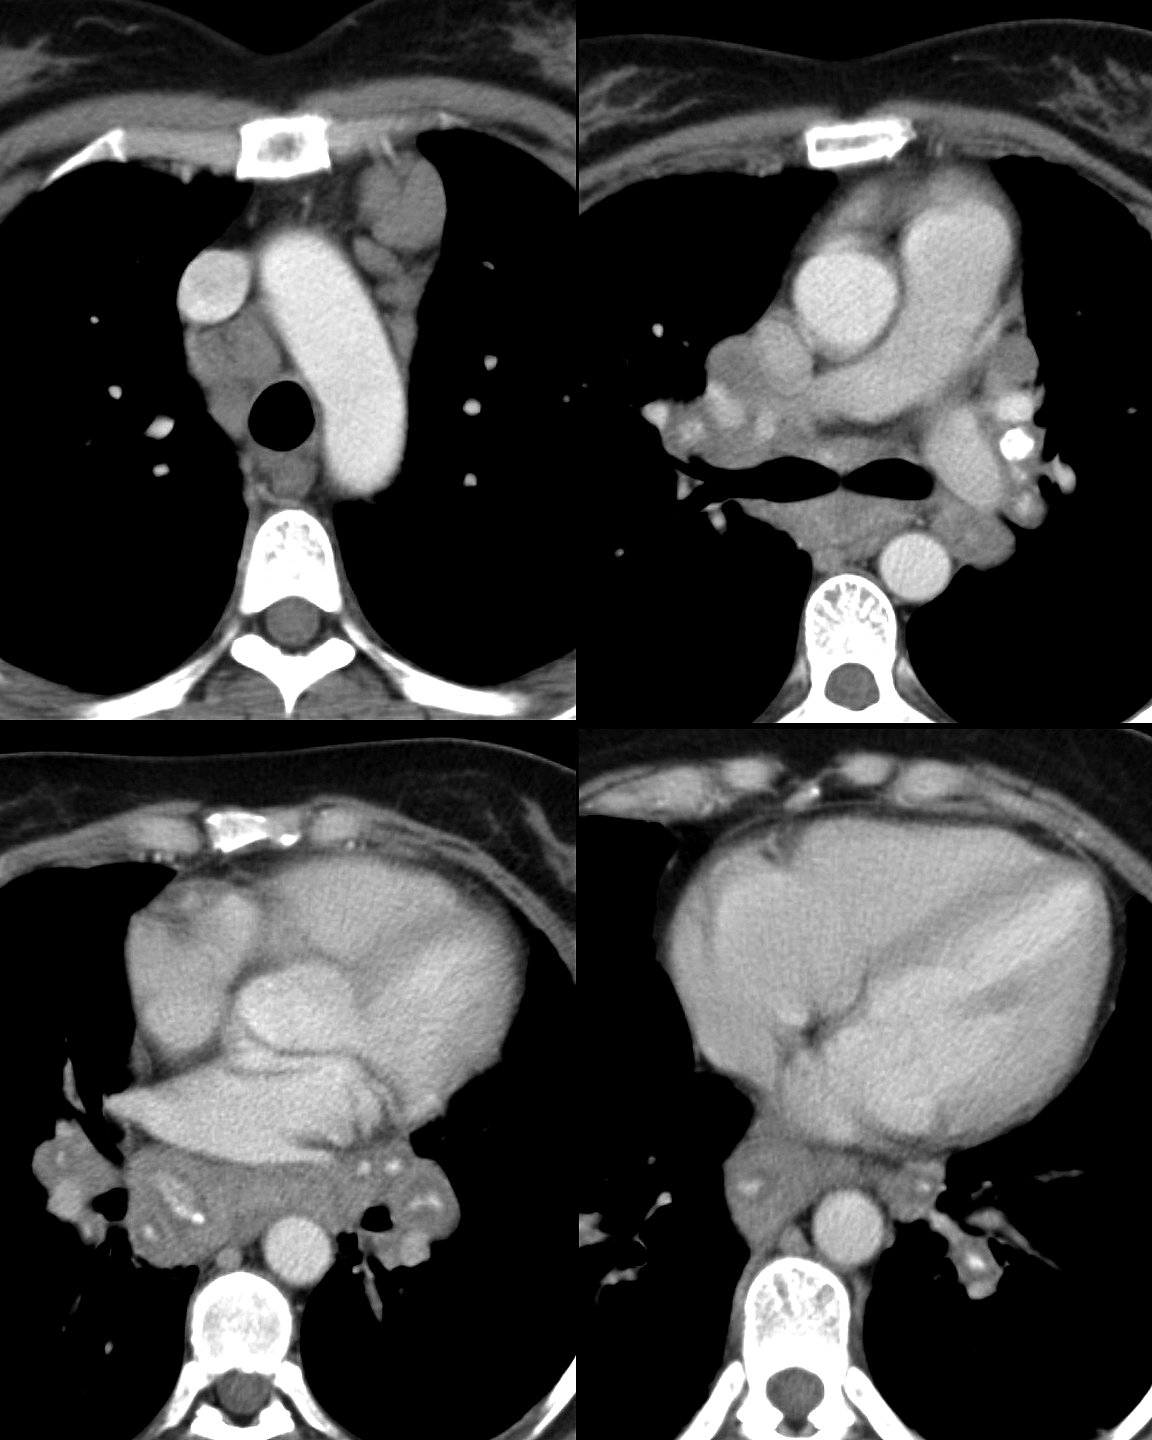

Sarcoid nodes with calcification